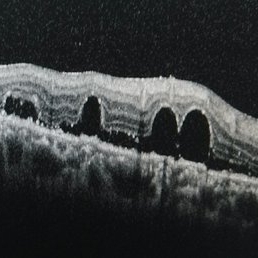

Perfluorooctane Drops Under the Retina

Perfluorooctane drops under the retina.

Condition/keywords: perfluorooctane